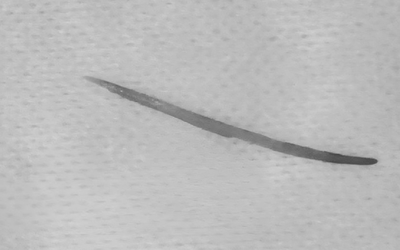

Người đàn ông 60 tuổi liên tục chảy máu mũi, bác sĩ gắp ra thứ "đáng sợ" bên trong

Người bệnh cho biết, ông thường xuyên đi lội suối gần nhà để làm việc. Cách đây vài ngày, ông bắt đầu thấy ngứa, khó chịu và chảy máu mũi kéo dài.